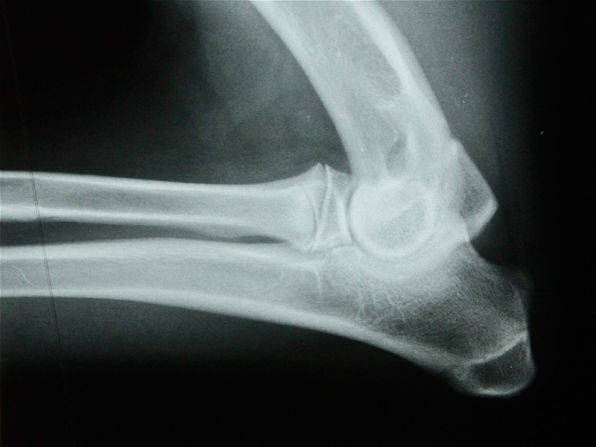

Dépistage de la dysplasie de coudes

Dysplasie du coude

Explications et point sur les denieres avancées en connaissances des origines, mécanismes, et traitements de la pathologie. Article du Dr Jean-Marc Wurtz, 2021.